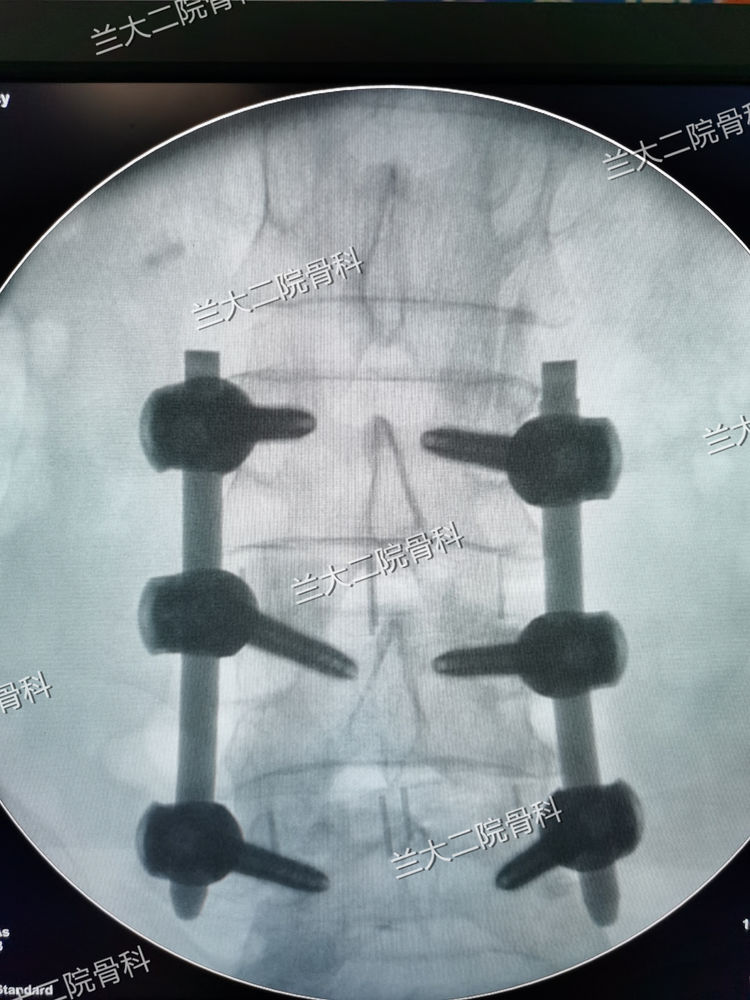

经皮钉固定